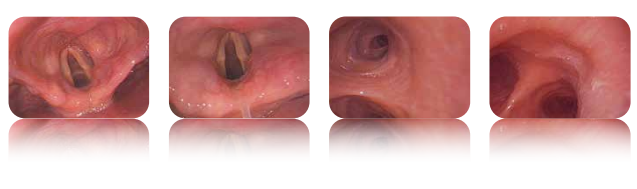

澳华可视喉镜MBC-5是一款具有优越性能和多功能设计的医疗设备。它采用了全新的图像处理器成像技术,能够提供清晰、高清的图像。这使得医生能够更准确地观察患者的喉部情况。

澳华可视喉镜MBC-5的插入部外径最细可达到4mm,可以实现非常精细的检查,减轻患者的不适感。

澳华可视喉镜MBC-5在麻醉科、呼吸科、耳鼻喉科、ICU、急症科和常日病房等领域具有广泛的应用前景。它能够满足不同领域医生的需求,提供准确的诊断和治疗支持,为患者的健康保驾护航。